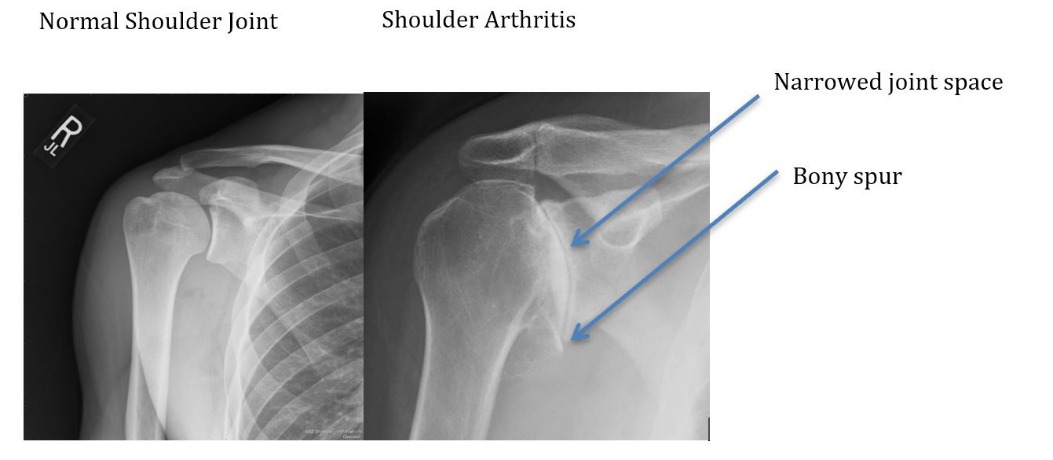

- X-rays

- Joint space narrowing

- Bone spurs

- Joint deformity